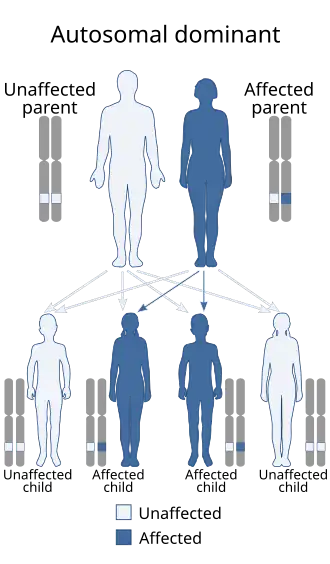

| Platelet storage pool deficiency is inherited in an autosomal dominant manner | |

Platelet storage pool deficiency can be acquired or inherited. Inheritance may be autosomal dominant or autosomal recessive, depending on the specific disorder.